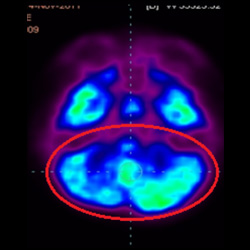

細(xì)胞治療前 PET CT 掃描顯示神經(jīng)組織中的藍(lán)/黑色區(qū)域,表明腦癱引起的大腦損傷。